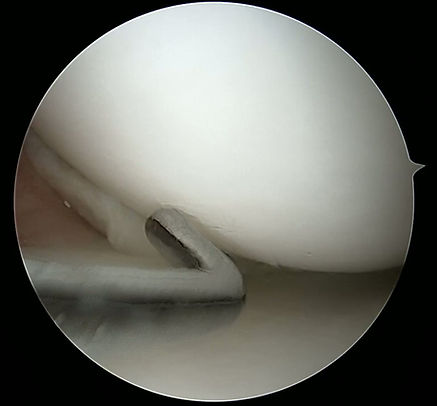

Chirurgie arthroscopique du ménisque

Lorsque la douleur, le gonflement et la limitation des mouvements persistent, l’arthroscopie devient une solution efficace.

La suture méniscale est privilégiée chez les jeunes patients et les sportifs, à condition que la lésion se situe dans la zone vascularisée du ménisque. Cette approche permet une guérison naturelle du tissu et préserve la fonctionnalité de l’articulation.

Si la lésion se situe dans une zone non vascularisée et ne peut pas être réparée, on procède à une méniscectomie partielle, qui consiste à retirer sélectivement le fragment endommagé.